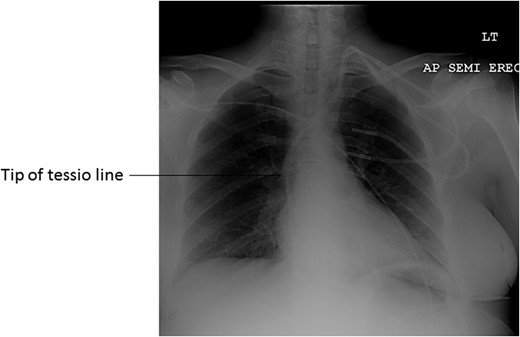

She was referred to the vascular surgery unit with the line in situ for 2 years following a failed attempt to remove the malfunctioning venous limb of the catheter on the renal unit. A chest X-ray showed the tip of the catheter at the level of the right atrium (Fig. 1). Following discussion at the multi-disciplinary meeting, the decision was made to attempt removal of the line by a combined endovascular and surgical approach under general anaesthesia.